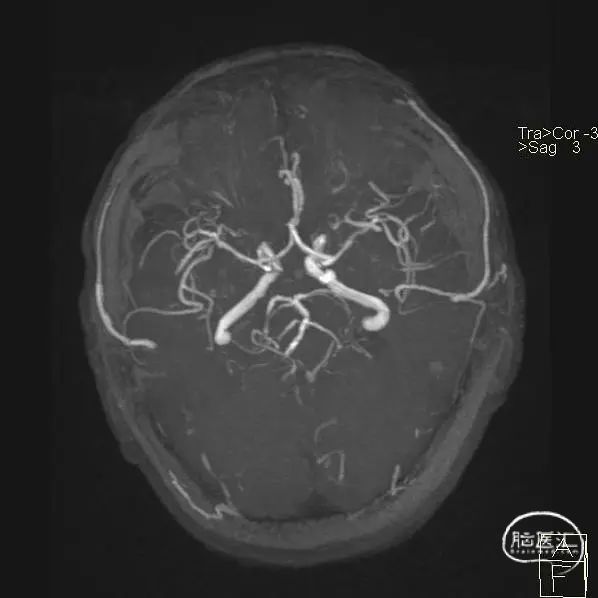

MR检查:

进行了常规化验,颈部超声检查、头部CT和MRI检查。

右侧脑室旁急性脑梗死(TOAST分型大动脉粥样硬化),左侧大脑后动脉P2、P3段可见中-重度狭窄,右侧大脑后动脉P2、P3段可见局限性轻-中度狭窄;

右侧颈内动脉C4、C6段狭窄,左侧颈内动脉C6、C7段局限性轻-中度狭窄。彩超提示右侧椎动脉起始段探测不清,不排除狭窄可能,左侧椎动脉阻力高,不除外远端闭塞可能;